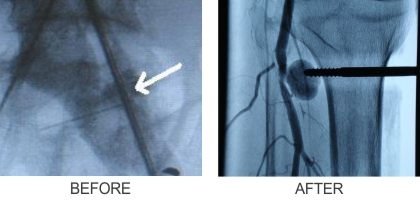

Angioembolisation for bleeding after fracture fixation

Endovascular procedures: These are minimally invasive procedures that use catheters and other devices to treat injuries to blood vessels from inside the vessel, without the need for an open surgical incision. The use of covered scents or endografts has revolutionized the management of large vessel trauma as the bleeding can be controlled while maintaining the potency of the vessel. Coil embolisation is another technique suitable for smaller vessel trauma, in which small microcatheters are passed into the bleeding vessel and special coils or glue is injected to control the bleeding.